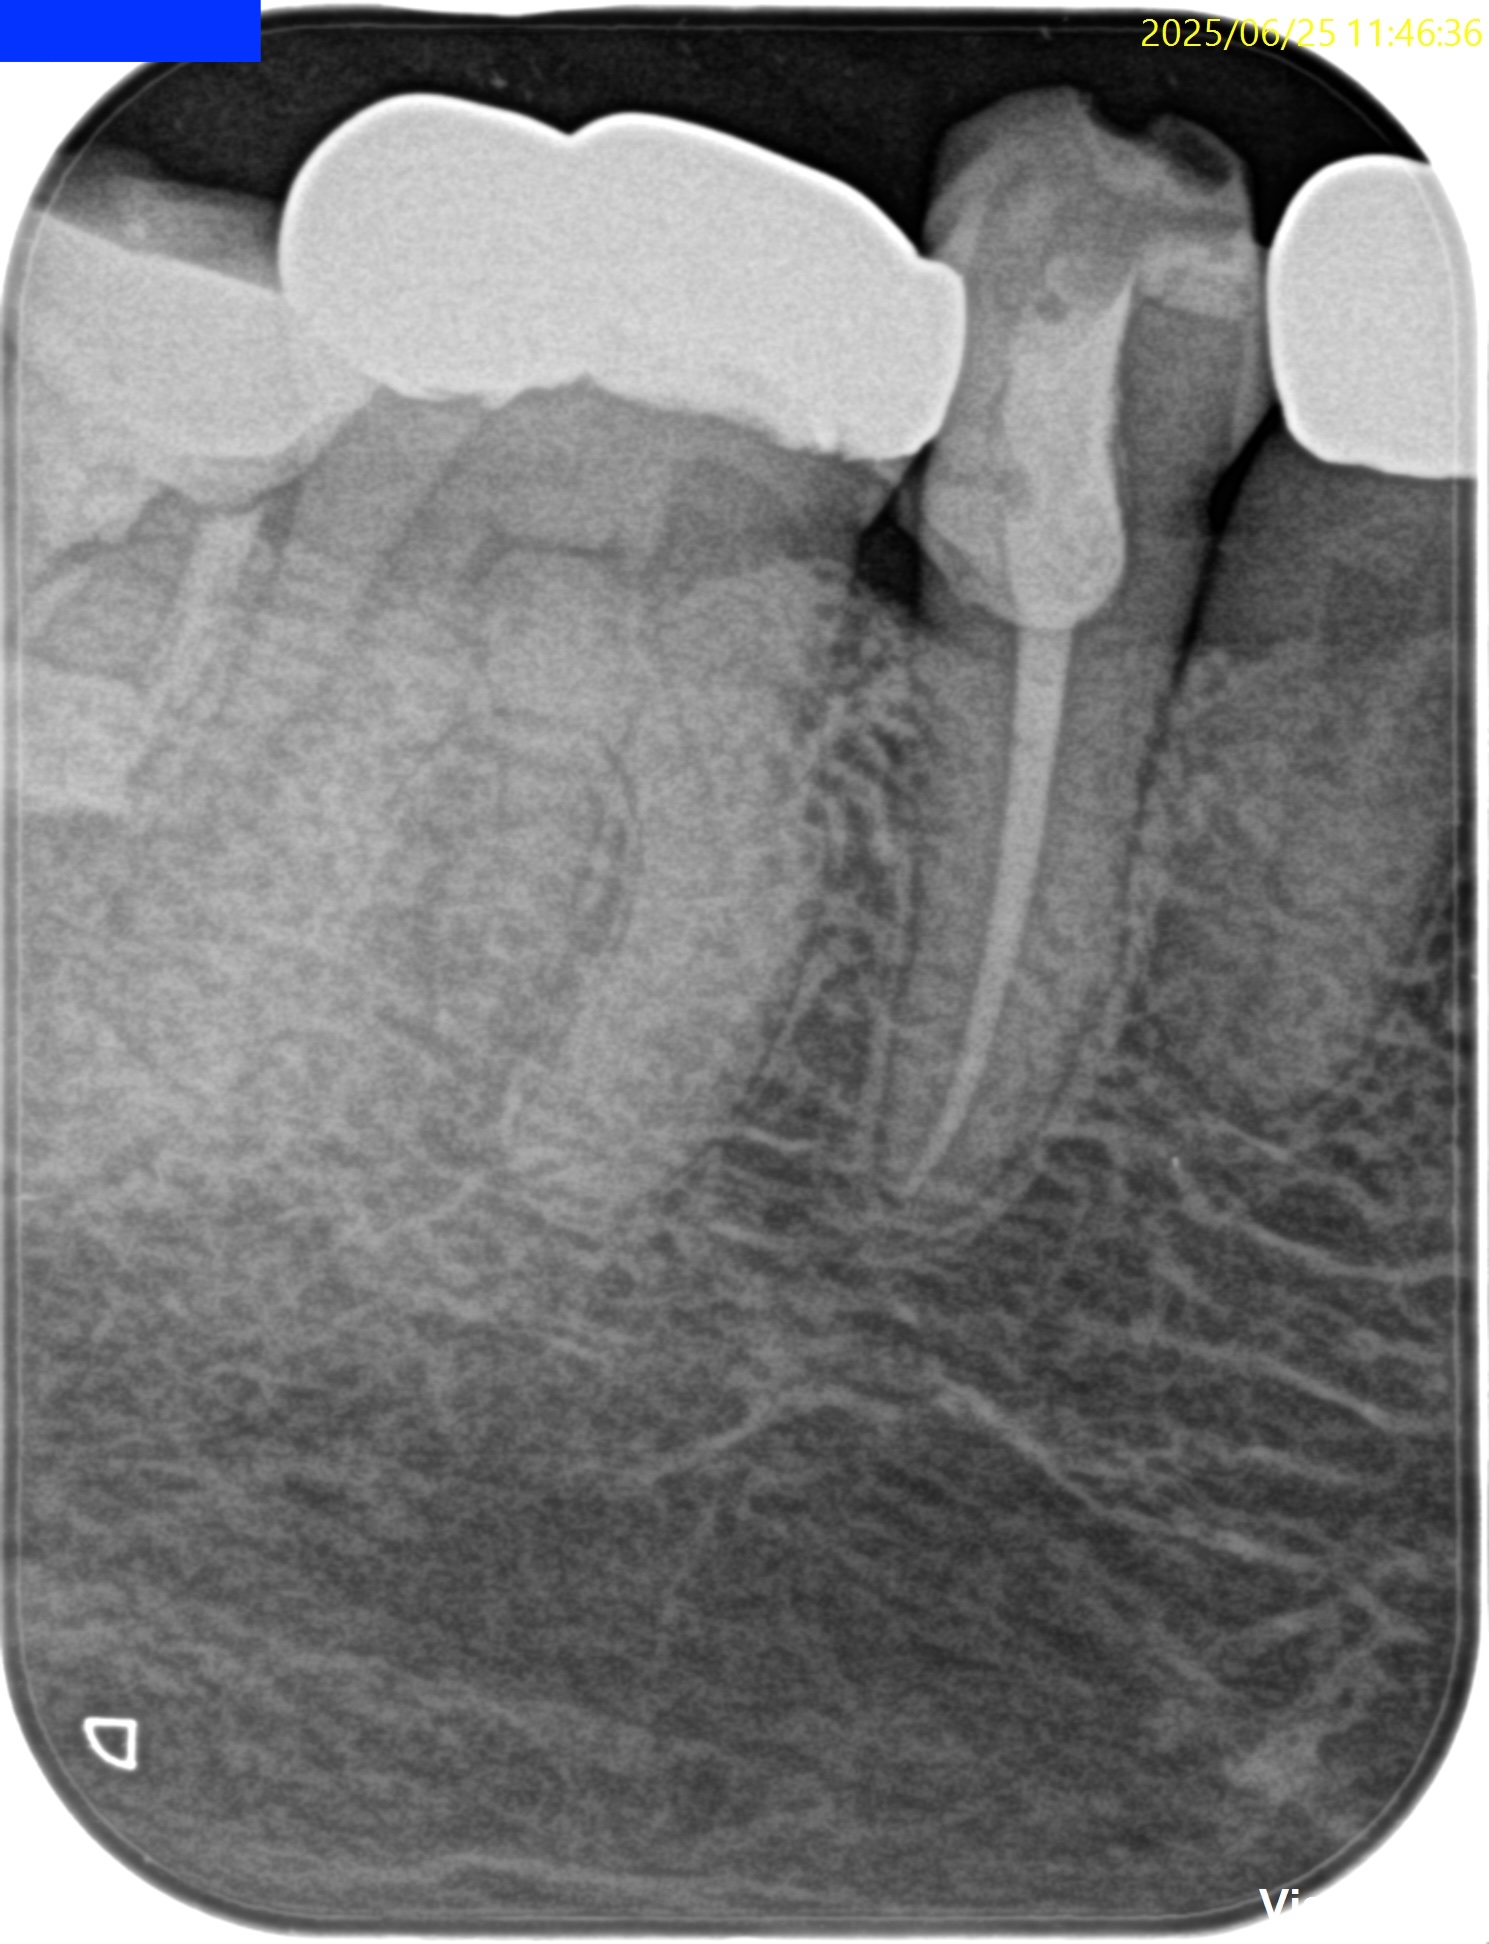

PA(2025.6.25)

検査でなく、PAで初めて患歯が#29だとわかる。

歯髄に迫る大きな虫歯が保険の修復物の下部にある。

CBCT(2025.6.25)

が、根尖病変はない。